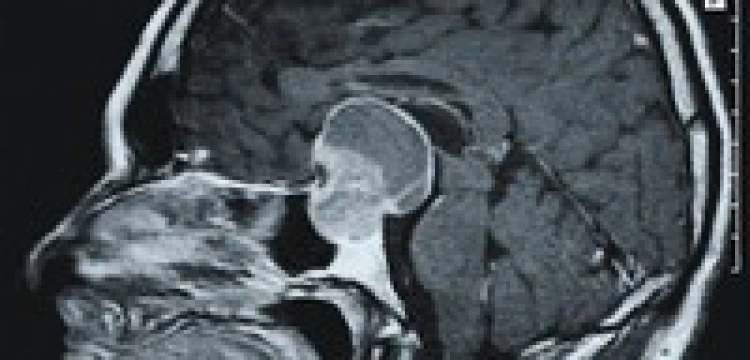

Mężczyzna od siedmiu lat sparaliżowany, do tej pory nie mógł kontaktować się z otoczeniem. Tak się tylko wydawało – jego mózg bowiem funkcjonuje. Dzięki zastosowaniu rezonansu magnetycznego okazało się, że rozumie zadawane mu pytania. A nawet może na nie odpowiadać – myśląc o graniu w tenisa (działania aktywne) potwierdza, myśląc o oglądaniu przedmiotów znajdujących się w jego domu (działania pasywne) – zaprzecza.

Naukowcy zadali choremu kilka pytań dotyczących jego rodziny, na które odpowiedział poprawnie. - Nasze badanie wykazało, że pacjent nie tylko jest w stanie wegetatywnym, ale, co ważniejsze, pierwszy raz od kilku lat uzyskał szansę na komunikację ze światem zewnętrznym – twierdzi dr Adrian Owen z Uniwersytetu Cambridge.